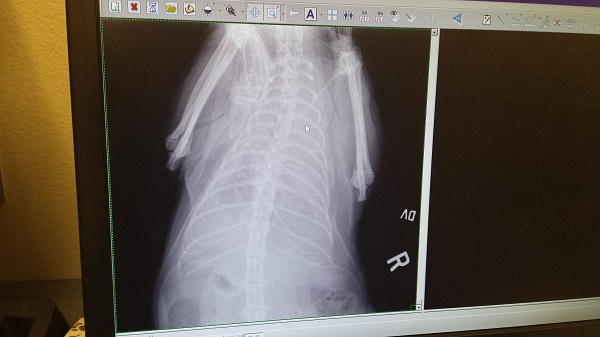

But he also told us that he did not wish to keep his appointment for Thursday’s x-ray/fluid re-check. As heartbreaking as this was to us, it made sense, and it wasn’t unexpected.

I called Dr. M., anyway, to talk about the Thursday follow-up appointment. He explained that if Ronnie James had accumulated enough fluid to be tapped, the radiologist would have to insert the needle into each pocket in order to aspirate enough of it to relieve the pressure around the lungs. This would create even more pockets for fluid to fill in the pleural cavity. At the rate Ronnie James had been accumulating fluid in the hospital up until the moment he was released, the likelihood of finding a tappable volume of fluid on Thursday was 99.9%.

So yesterday afternoon, Ronnie James underwent anesthesia again, and Dr. M. and the radiologist performed a lymphangiography. This procedure allowed Dr. M. to see whether we’d have a shot at the one last surgical option available for chylothorax: cisterna chyli ablation. The study results showed that the surgery would be irrelevant, since the problem was not leakage from the thoracic duct. The thoracic duct ligation surgery had been effective. The fluids were coming from somewhere else, likely from the pleura, as a result of pleural fibrosis. We are out of options.

On Thursday, we’ll take him back to Dr. M. for an x-ray to see where we are with the fluids. We’ll probably have to make The Decision at that time… for real, this time.

His chest cavity just keeps filling up with fluid.

As I said, it’s not chyle. Rather, we’re looking at some sort of nondescript, inflammatory-ish fluid, and at this point, no one can say with certainty what it’s all about. A little bit of such fluid could be normal following a surgery. It could be caused by the chest tube, itself, even. But the amount of fluid we’re talking about here is well out of range. Ronnie James’ case is a complicated one, and it’s tough. We’re still battling the ripple effect of his contact with that venomous Pine Processionary caterpillar.

This current iteration of pleural effusion could be a fluke, as in, maybe a “pocket” of fluid resulting from the surgery just released all at once over the night (that was Wednesday night). Or, it could be something scarier, such as his pleura lingering in a self-perpetuating cycle of emitting fluid. Whatever the case, we can’t bring him home until the pleural effusion stops, since his chest tube needs to stay in place in order to drain the excessive fluids.

This development resulted from yesterday’s trip to the vet, when it was found that fluid has filled his pleural cavity again. His chylothorax persists with an aggression that’s frightening. A chylothorax-specific surgery might be able to stop the process; it’s actually a combination of procedures: Thoracic duct ligation plus pericardectomy. This is our next step, and it’s our last.

We were told that the success rate for this surgery is 80% for cats, which is encouraging… but we’re not sure if the Wrah-Wrah will have a chance to try for those odds. We won’t know until Dr. M. opens him up today and examines him. If the developing pleural fibrosis (a complication of chylothorax) is still mild enough to be survivable, Dr. M. will move forward with the surgery. If the pleural fibrosis turns out to be beyond-hope bad, on the other hand, he’ll drain Ronnie James’ chest for the last time and close him up. We’ll have the “end of life” discussion. It will be time to address the details of The End.